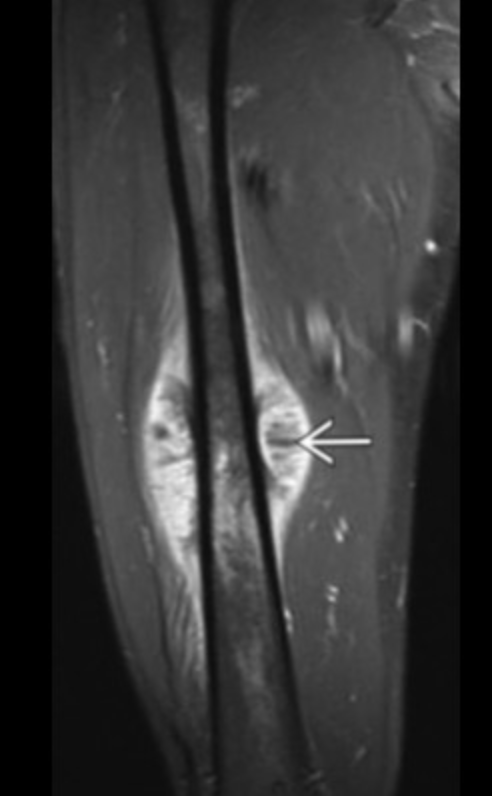

Osteoid Osteoma

• Basically looks like a target

• Central sclerotic area with peripheral lucency

• Hot on bone scan